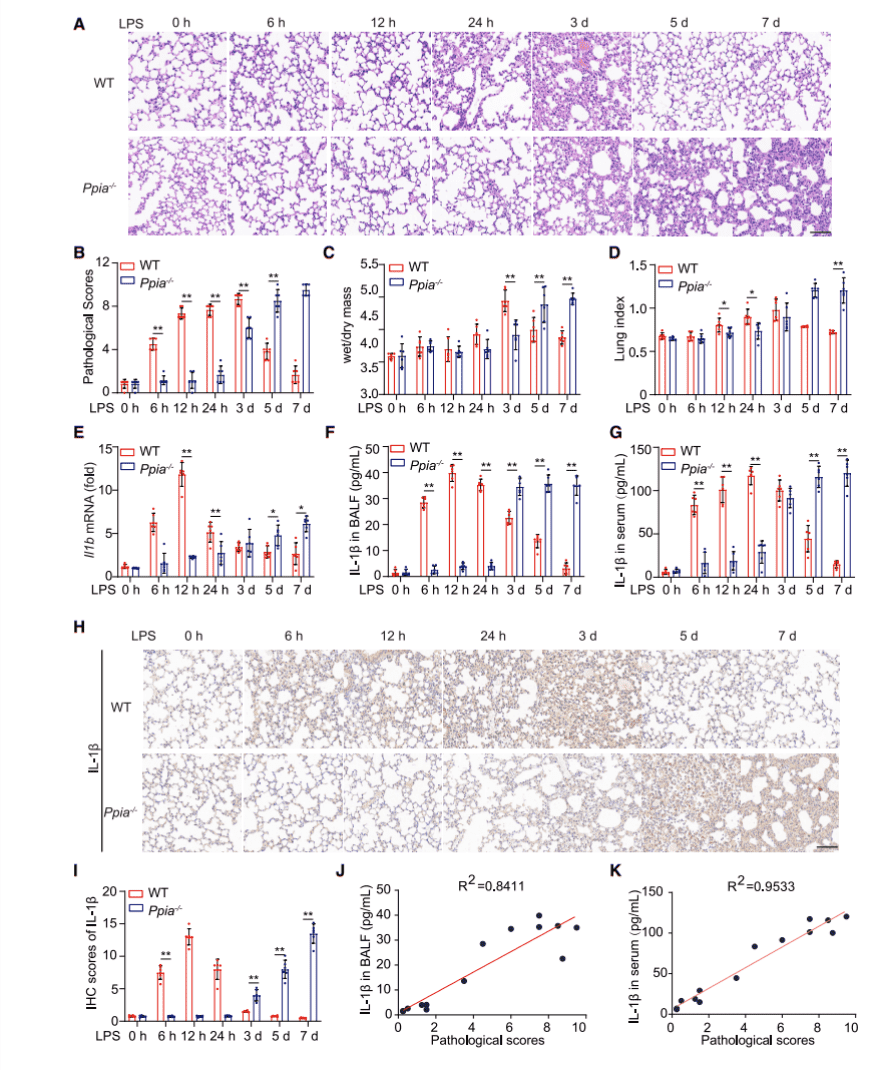

Ppia-/- mice were purchased from Jackson Laboratory and together with wild-type mice (WT) to form lung inflammation mouse models with different time points after LPS induction for 0, 6h, 12h, 24h, 3d, 5d, 7d. First by histopathological staining experiments (Fig. 1A), lung sections from mice at different time points were pathologically scored (Fig. 1B) and, at the same time points, lung dry and wet mass changes (Fig. 1C) and lung index (Fig. 1D) were statistically analyzed and their results were found to be astonishingly similar, thereby illustrating that CypA encoded by Ppia plays different roles at different stages of inflammation.

Because cytokines play an important role in the inflammatory response, to examine how these cytokines behave in the inflammatory models, researchers extracted mRNA from the lungs, bronchoalveolar lavage fluid (BALF), and serum of Ppia-/- and WT mice, respectively, then examined the expression of pulmonary cytokine Il1b (Figure 1E), as well as secretion cytokine IL-1β from BALF (Figure 1F), serum (Figure 1G) and lung (Figures 1H and 1I) by qPCR, ELISA and immunohistochemistry experiments. It was found that the expression of these two cytokines in different parts of WT mice was higher than in Ppia-/- mice at 6h, 12h and 24h, while at 3d, 5d and 7d, the expression of these cytokines was reversed. In addition to this, researchers also examined the expression amount of other cytokines in the various sites (see supplemental figure). Taken together, all experimental findings suggest that in the mouse model of LPS-induced inflammation, CypA acts primarily by regulating IL-1β expression to control its role in different stages of inflammation.

Figure 1. CypA regulates LPS-induced lung inflammation, depending on IL-1b expression